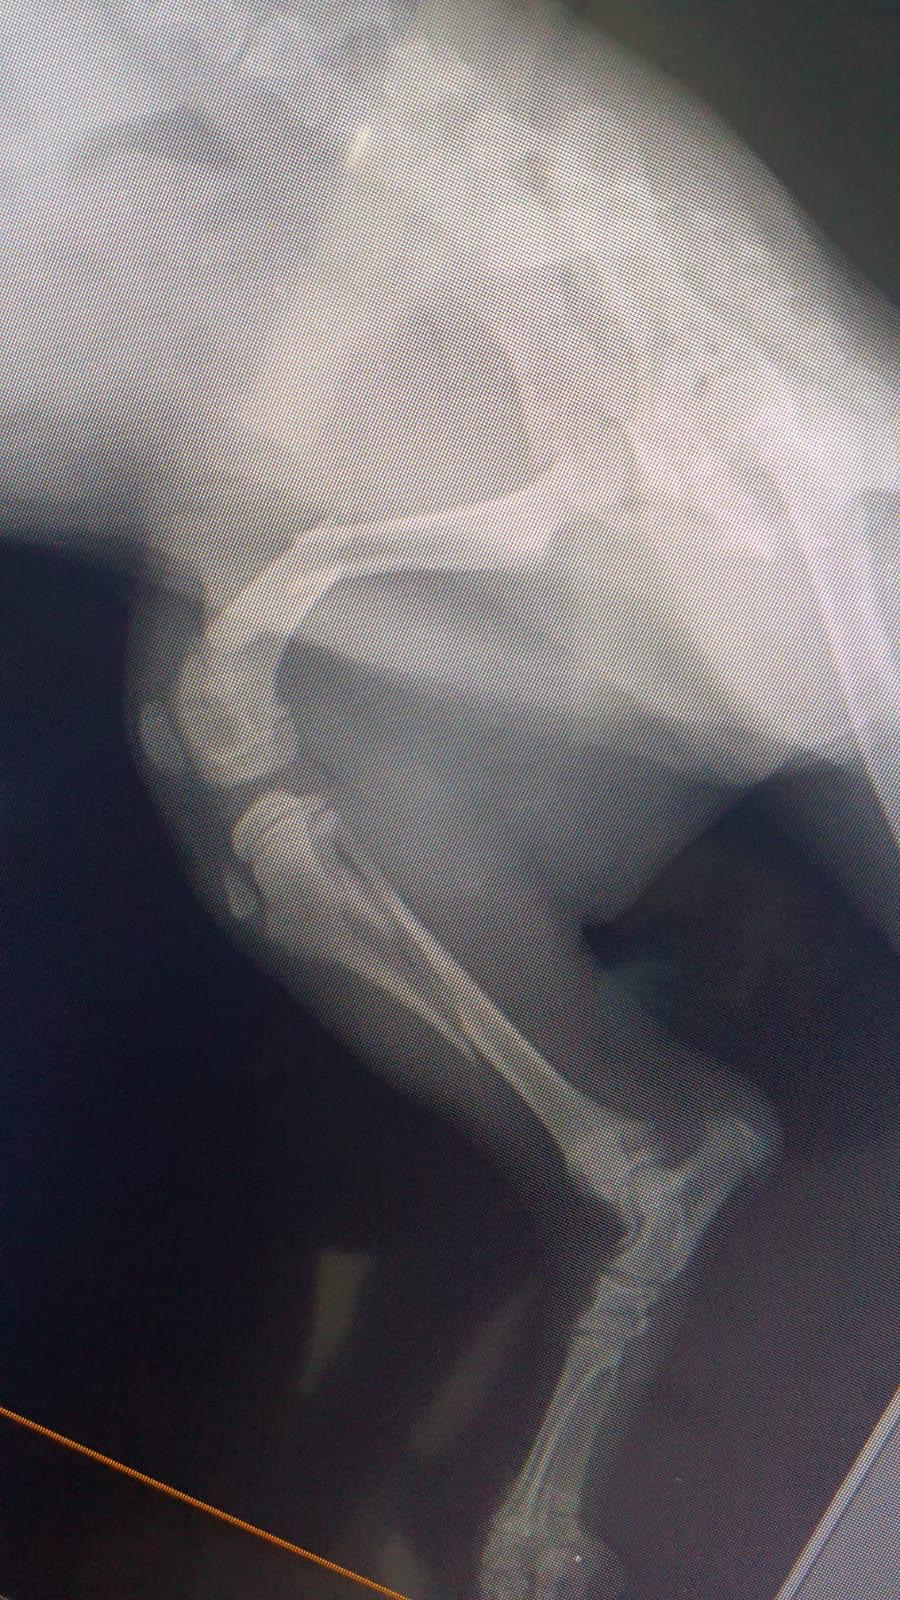

LANDON a été trouvé chiot et blessé sur la route (patte cassée), au Liban. Recueilli et soigné par le Refuge de l’association BETA LEBANON.